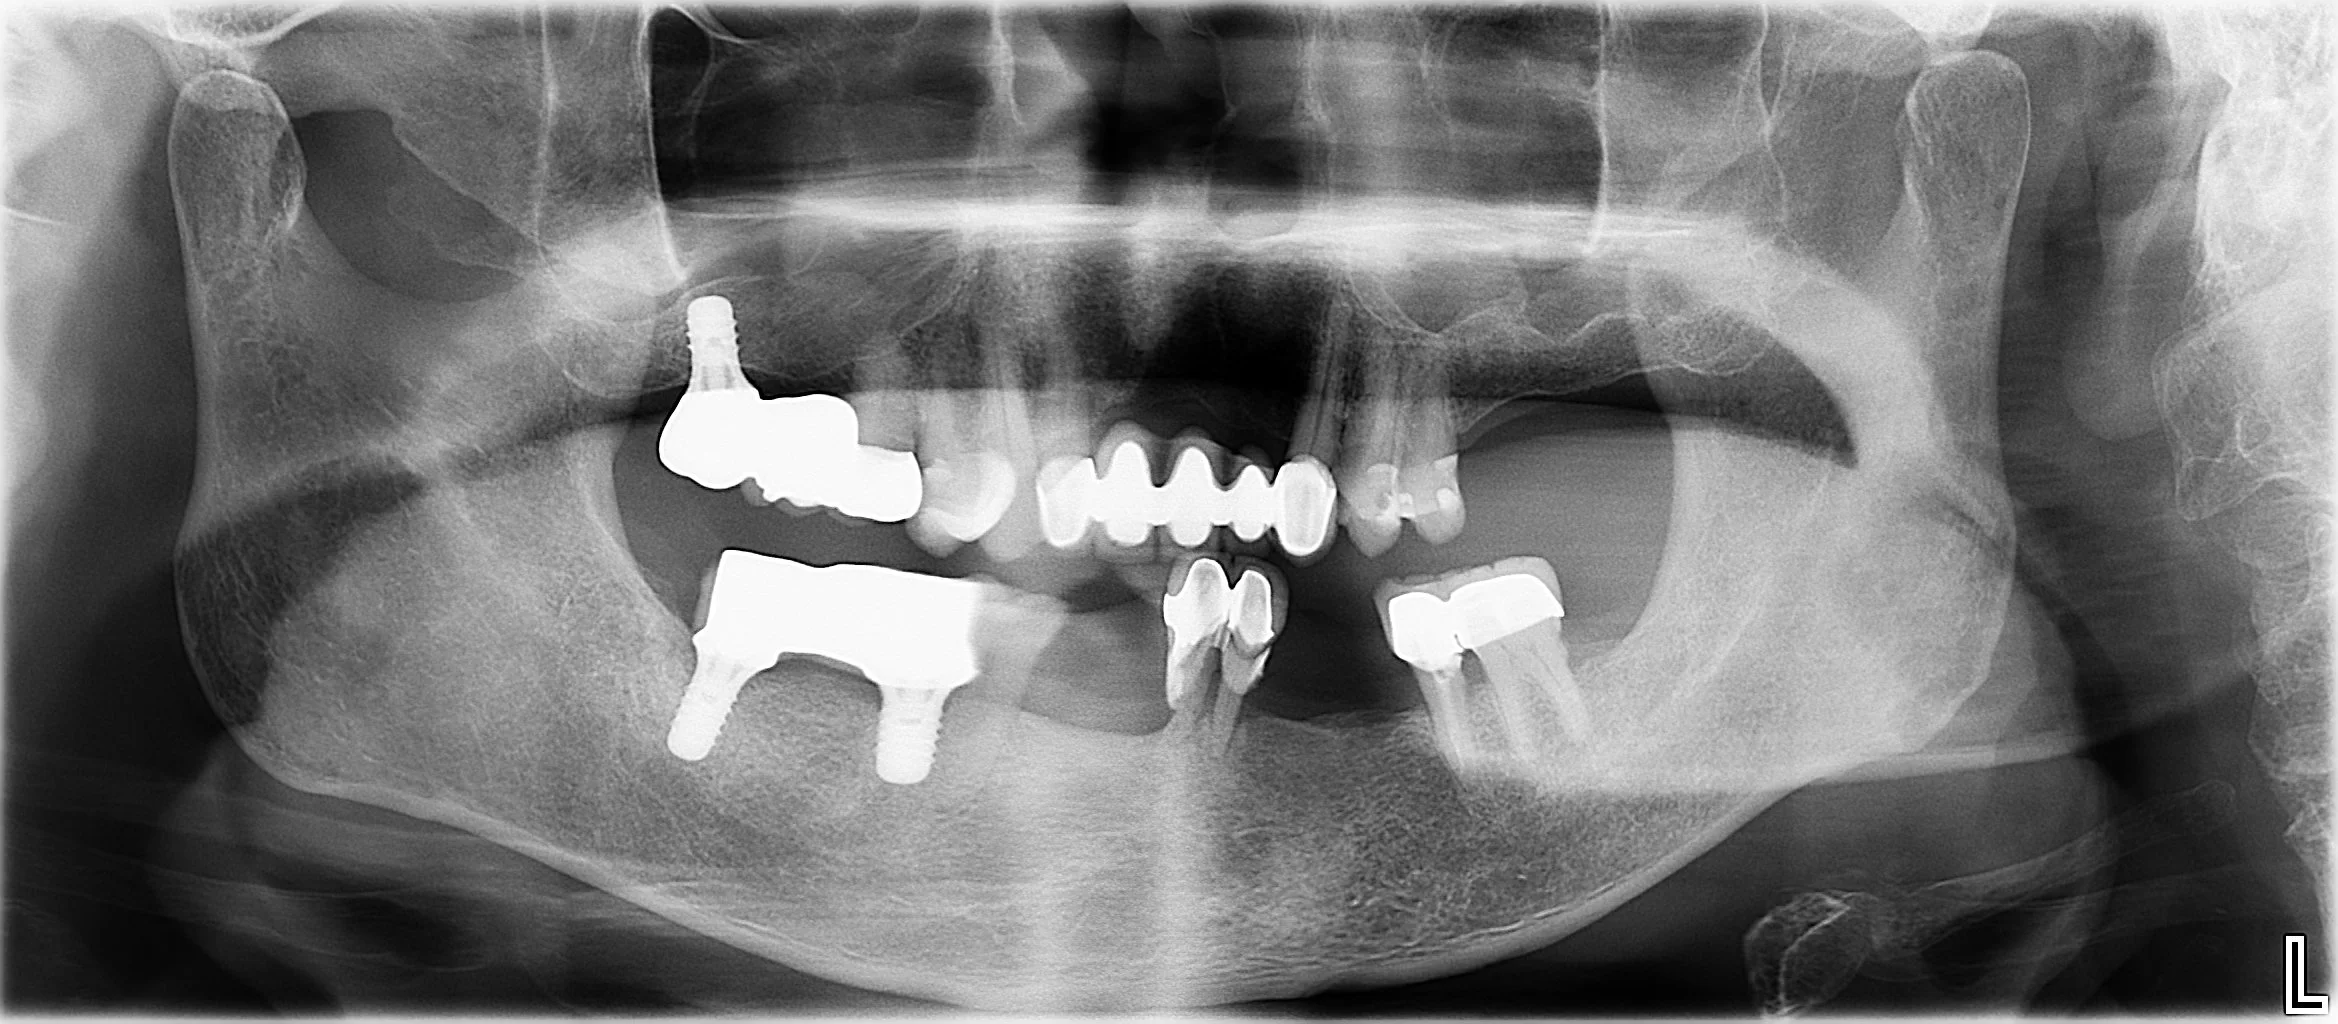

DSC_0935.JPG

Panoramic dental X-ray showing upper and lower teeth with some dental restorations, including crowns and fillings, and the surrounding jawbone.

DSC_0285.JPG

AFTER

Dental X-ray showing several dental implants, crowns, and bridges in the upper and lower jaw.

MULTIPLE TEETH REPLACEMENT

(WITH DENTAL IMPLANTS)